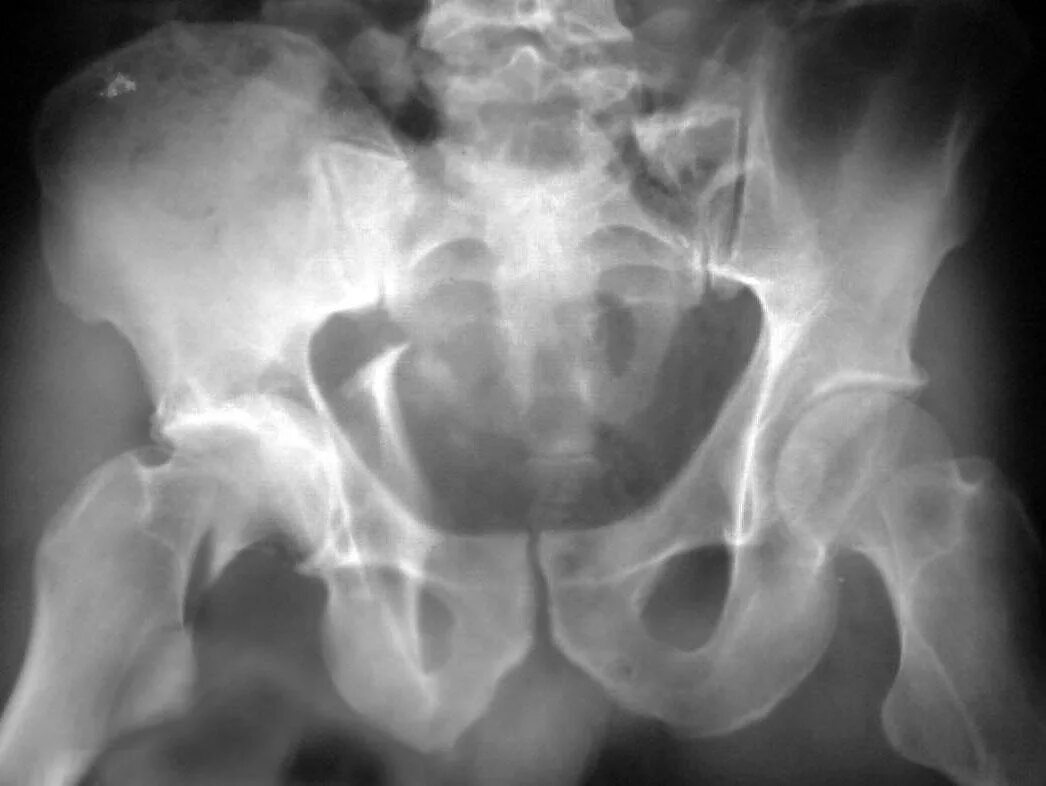

Перелом заднего